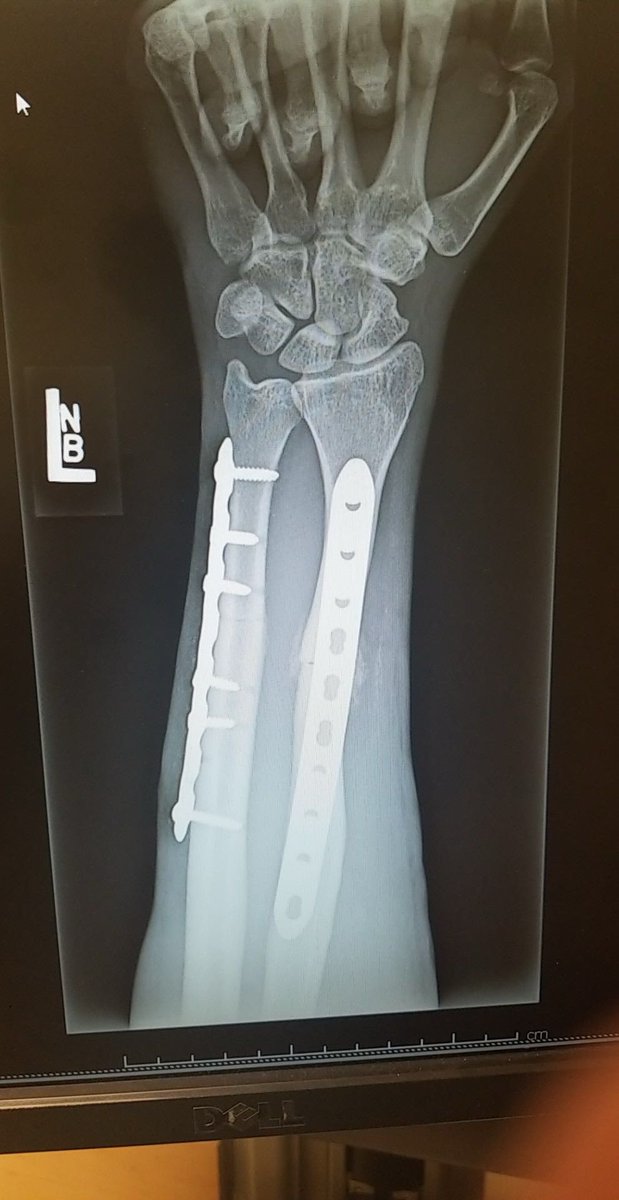

Bro as someone who went through something similar, two 6 inch plates, 14 screws, and a piece of my elbow to fix it, then all the hardware out 6 months later and a full bone graft.

Went to 5 different doctors before finding Alhidad Ghiassi. He’s now a private practice hand and arm specialist, but one of the best, he’s in LA, highly recommend